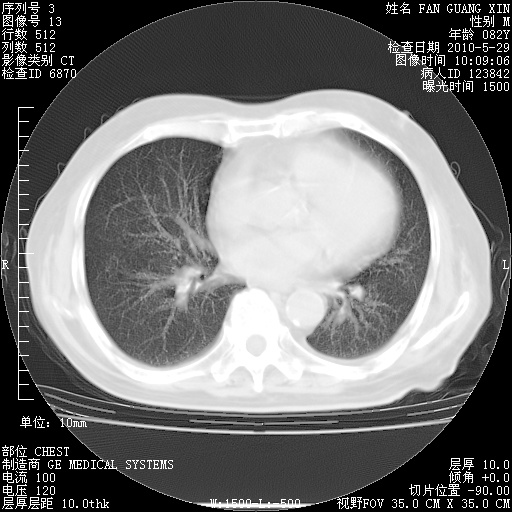

治疗3周后的肺部CT纵隔窗

再治疗10天后的肺部CT

再治疗10天后的肺部CT 纵膈窗

阅读此次胸部CT,肺间质渗出性改变较入院时有吸收。目前从体温、白细胞、中性分叶明显增高,肯定存在细菌感染(发生医院感染哦,若无消化道及泌尿系统等感染的依据,肺部感染可能大)。若你院头孢哌酮舒巴坦钠耐药率较高,同意你的方案,若48小时体温仍高,可考虑使用碳青霉稀类抗菌药物,同时可予超声雾化、注意滴数时加大液体量。白蛋白33.30g/L较低哦,需加强营养等支持治疗。